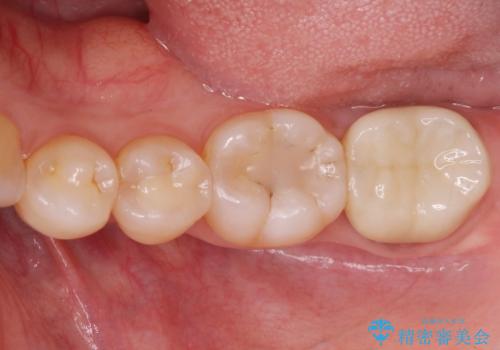

歯の噛む面が黒い。

- 歯の噛む面が黒いとのことで来院。

過去にプラスチック樹脂の治療がされており、プラスチックと歯質の隙間に汚れがたまり黒くなっていました。

劣化して黒くなりたくない、虫歯の予防がしたいとのご希望だったのでセラミックインレー(e-maxインレー)による治療を行いました。